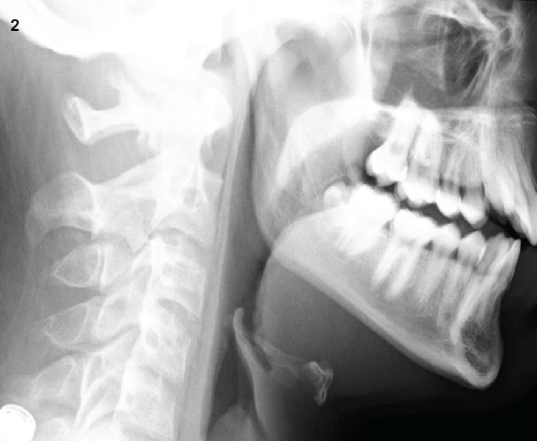

A 45-year-old man presented to the office of a primary care provider (PCP) with a 2-month history of a noticeable lump in his right neck.

A 42-year-old woman with no known relevant past medical history presented with a sudden onset of slurred speech and right-arm weakness.